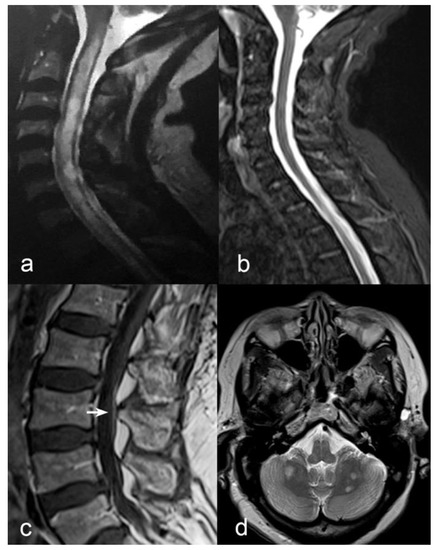

2. Results